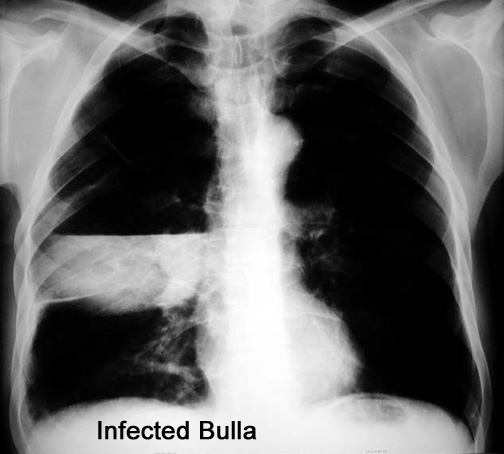

Case 9

Follow up

Spine

Neck

Labeled Image What are the pulmonary manifestations of Ankylosing spondylitis?